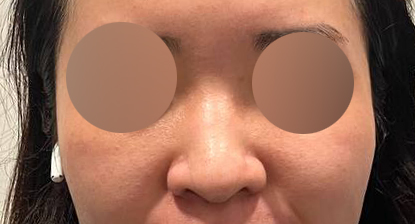

코성형 1개월차 찐 후기:)

1개월차 찐 후기 올려요 :)

지금 제 코는 만족스러우며 아직 한달지만

주마다 코 모양이 달라지는걸 느끼고 있습니다!

유영문 원장님이 아주 잘됬다며 칭찬해주실때마다

더 이뻐지길 기대하고 있어용 ㅎㅎㅎㅎ